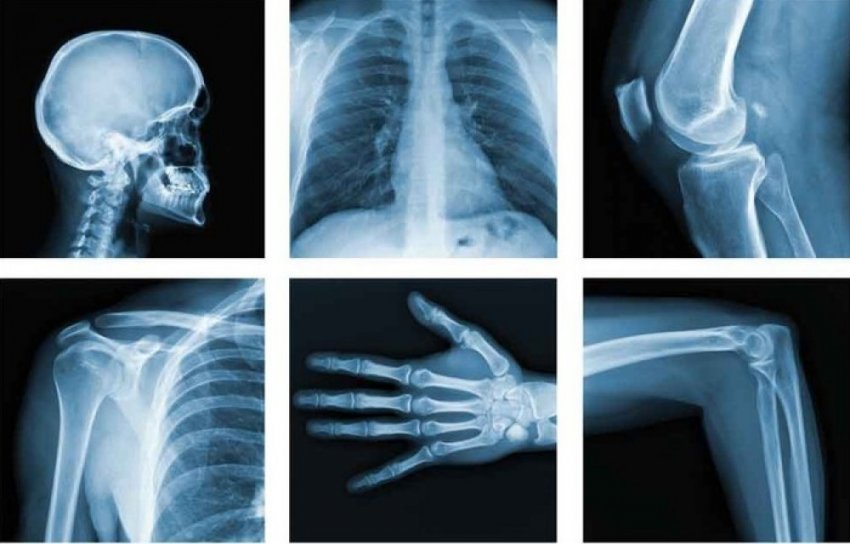

Рентгеновское излучение в медицине

Способность рентгеновских лучей просвечивать материальные объекты не только дает людям возможность создавать простые рентгеновские снимки, но и открывает возможности для более продвинутых средств диагностики. К примеру, она лежит в основе метода компьютерной томографии (КТ).

Внутри кольца, в котором лежит пациент, вращаются источник рентгеновских лучей и приемник. Полученные данные о том, как ткани тела поглощают рентгеновские лучи, реконструируются компьютером в 3D-картинку. Метод КТ особенно важен для диагностики инсульта, и хоть он и менее точен, чем магнитно-резонансная томография головного мозга, зато требует гораздо меньше времени.

Сравнительно новое направление, которое развивается сейчас в микробиологии и медицине, — применение мягкого рентгеновского излучения. При просвечивании живого организма оно позволяет получать изображение кровеносных сосудов, подробно изучать структуру мягких тканей и даже проводить микробиологические исследования на клеточном уровне.

Рентгеновский микроскоп, использующий излучение разряда типа пинч в плазме тяжелых элементов, дает возможность увидеть такие детали строения живой клетки, какие не видит электронный микроскоп даже в специально подготовленной клеточной структуре.

Один из видов лучевой терапии, применяемой для лечения злокачественных опухолей, использует жесткое рентгеновское излучение, что становится возможным благодаря его ионизирующему воздействию, разрушающему ткань биологического объекта. В этом случае в качестве источника излучения используется ускоритель электронов.